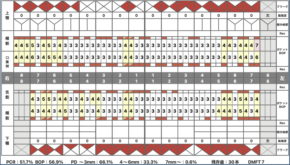

上記は、日本歯周病学会の歯周病の新分類の指標になりますが、

『歯周病の重症度』をステージ分類し

『歯周病の進行のスピード』をグレード分類します。

歯周病の検査とは

歯周ポケットと呼ばれる歯と歯ぐきの境目の深さと、そこからの出血の有無を検査します。

様々な検査データは

歯科医院側での診断をするための大切なデータである一方で、患者さんのデータであり

『患者さんとの情報共有』と『患者さんのモチベーションの獲得』